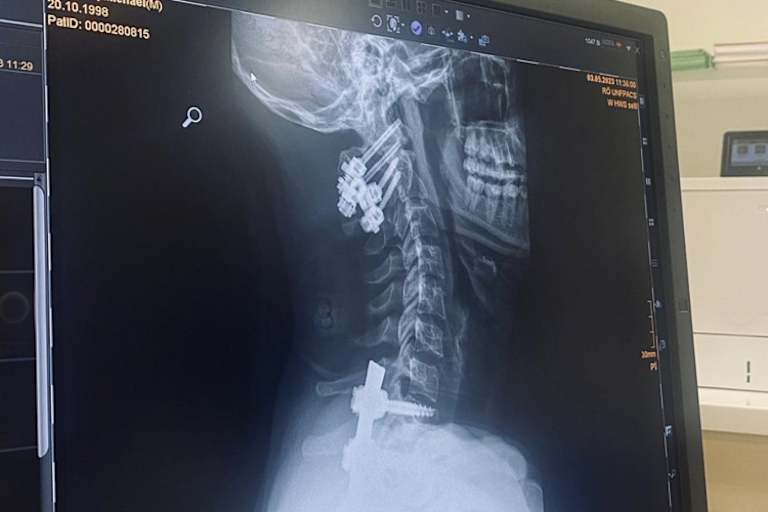

Inzwischen ist der schwere Unfall von Michael Sandner in Pietramurata mehr als 6 Wochen her. Der 24-jährige Österreicher war in der dritten Runde des Großen Preises von Trentino schwer gestürzt und hatte sich dabei schwerste Wirbel-, Schulter- und Hüftverletzungen zugezogen. Besonders kritisch war der Bruch des Atlaswirbels C1. Sandner musste in den ersten Tagen intensivmedizinisch versorgt werden.

Die OP der Halswirbel C1 und C2 sowie die Brustwirbel T3 bis T10 dauerte insgesamt 10 Stunden. Die Wirbel wurden mit Metallschienen verbunden und verschraubt, um die Stabilität der Wirbelsäule herzustellen und eine Heilung der Knochen zu ermöglichen. Sandner hat nun in den sozialen Medien ein Foto seines Röntgenbildes sowie der Nähte nach der OP veröffentlicht und kommentierte die Bilder mit den Worten: "Es geht Schritt für Schritt in die richtige Richtung." Sandner hatte bei seinem Crash in Pietramurata Glück im Unglück, dass er den Unfall ohne Lähmungserscheinungen überstanden hat. Was die Beweglichkeit und Belastbarkeit des Oberkörpers insgesamt angeht, liegt noch ein langer Weg der Rehabilitation vor dem 24-Jährigen.